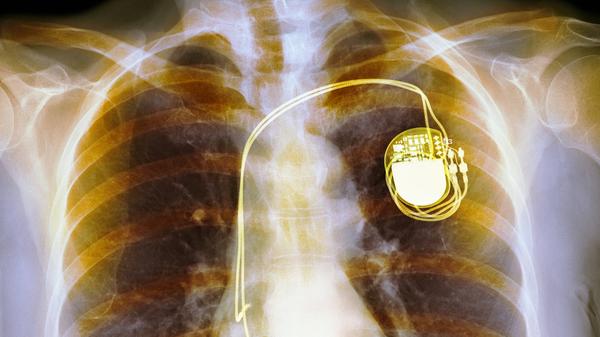

Das Gerät, etwa so groß und schwer wie zwei aufeinanderliegende Zwei-Euro-Münzen, wird über einen Hautschnitt unterhalb des Schlüsselbeins eingesetzt. Von diesem Aggregat führen Elektroden (Sonden) durch eine Vene in die Herzkammer oder Vorkammer. Diese Sonden – je nach Bedarf und Zusatzfunktionen eine, zwei oder auch drei – regen das Herz elektrisch zum Schlagen an, wenn es Störungen gibt.